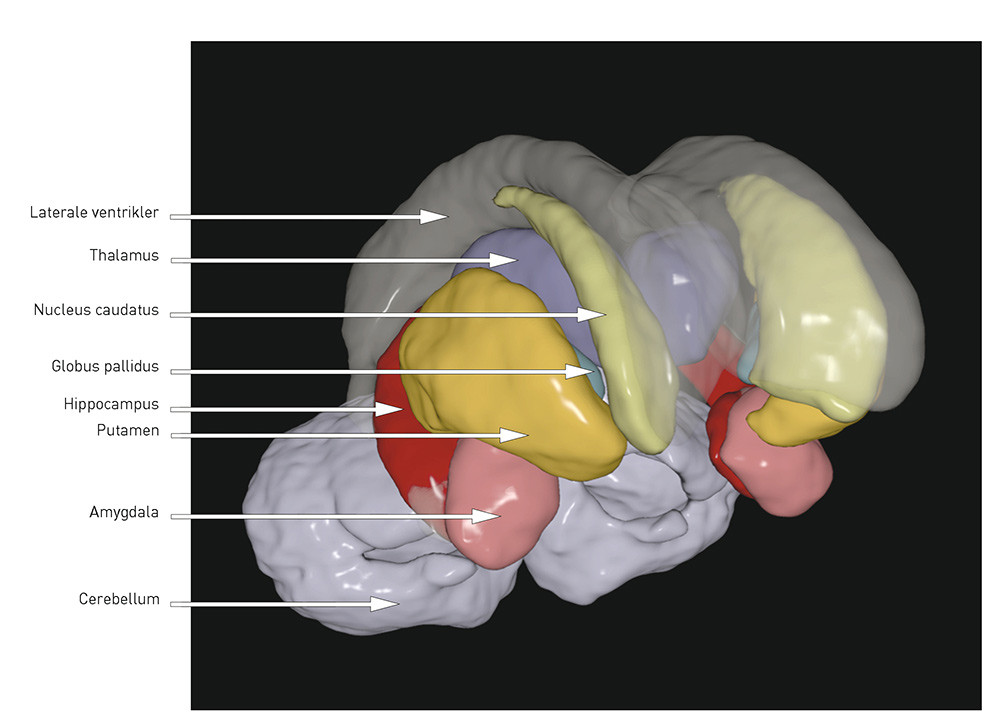

Når totalvolumet er mindre og ventriklene større, kan man spørre seg om det er visse regioner eller strukturer der volumreduksjonen er mer uttalt. Her følger en kort oversikt over de best replikerte funnene (for illustrasjon, se fig 1 og fig 2):

Hippocampus ligger medialt i temporallappen og er viktig for verbal innlæring og hukommelse. Denne er jevnt over rapportert å være mindre hos pasienter med schizofreni enn hos friske kontrollpersoner (4, 9), noe vi også har rapportert fra to skandinaviske kohorter (7, 11, 12). I en nylig publisert metaanalyse av 44 MR-studier ble effektstørrelsen funnet å være moderat (d = –   0,48 og –   0,53 for henholdsvis venstre og høyre hippocampus) (13), og det var ingen forskjell mellom førsteepisode og kronisk schizofreni. At forandringene var til stede ved sykdomsdebut, kan tyde på at hippocampusreduksjonen ved schizofreni er utviklingsrelatert. Volumreduksjonen kan representere tap av grå substans, og dette kan ha betydning for kognitive funksjoner som innlæring og hukommelse, som er vist nedsatt ved schizofreni (14).

Det er i flere studier, inkludert våre egne (7, 11, 15), og i metaanalyser (5, 16, 17) vist større volum av basalgangliene, spesielt uttalt i globus pallidus, ved schizofreni. Basalgangliene er dopaminfiberrike, og forandringer kan derfor være vanskelig å tolke siden strukturene påvirkes av antidopaminerge antipsykotika (18).

Thalamus, en midtlinjestruktur som grenser mot ventriklene, har vist seg å være mindre hos pasienter med schizofreni (19). I en metaanalyse er det vist effektstørrelse på d = –   0,32 (høyre) og d = –   0,33 (venstre) ved kronisk og d = –   0,45 (høyre) og d = –   0,48 (venstre) ved førsteepisode schizofreni (20). Thalamus fungerer som knutepunkt for hjernens kognitive prosesser, og en hypotese er at informasjonsflyten mellom ulike hjerneområder er forstyrret ved schizofreni (21).

Cortex er en innfløkt struktur med sulci og gyri. Nevronene i cortex er blant annet involvert i viljestyrte og kompliserte kognitive prosesser. De første MR-studiene påviste mindre volum av cortex, spesielt i frontal- og temporallappen (4). Volumreduksjonen er blitt replikert i flere senere studier og kan reflektere reduksjon av nevropil (umyeliniserte nerveceller, synapser og gliaceller), som vist ved nevropatologiske post mortem-studier (22). Mindre volum kan skyldes redusert tykkelse og/eller areal (volum = tykkelse x areal). I vår gruppes studie fra Oslo fant vi tynnere cortex samt mindre areal og volum ved schizofreni, der volumforandringene var «drevet» av tykkelsesreduksjonen (23). Dette stemmer overens med flere andre studier som viser tynnere cortex, mest uttalt frontalt og temporalt, ved schizofreni (24) – (26).